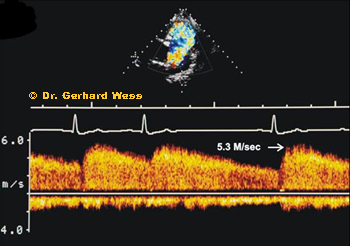

What does echocardiography show?

Doppler imaging is used to assess blood flow through the ductus and to estimate the pressure gradient between the aorta and the pulmonary artery.

CW Doppler image in PDA Continuous-wave Doppler helps estimate the velocity through the PDA and assess whether pulmonary hypertension may already be developing.